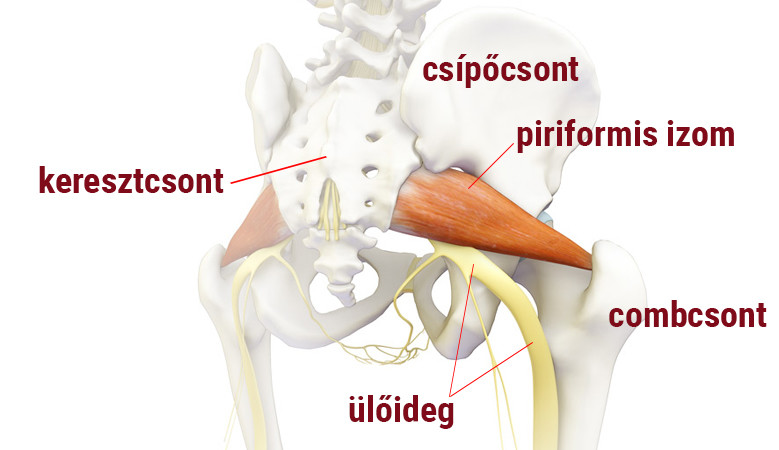

Csípőízületi gyulladás 1 2 fokos kezelés, Fontos tudnivalók a műtéti kezelés előtt:

A kezelés végezhető a térden, bokán, csípőn, vállon is. Az eddigi eredmények kimagasló javulást mutatnak a tünetek enyhülésében, a fájdalom csökkenésében, és ennek következtében bizonyos esetekben a protézis beültetés elkerülhető. Ez a könnyen kezelhető rendszer arra lett kifejlesztve, hogy a zsírszöveteket kinyerjék, akár 20 perc alatt feldolgozzák és ugyanazon sebészi eljáráson belül vissza is ültessék a kezelésre szoruló területbe.